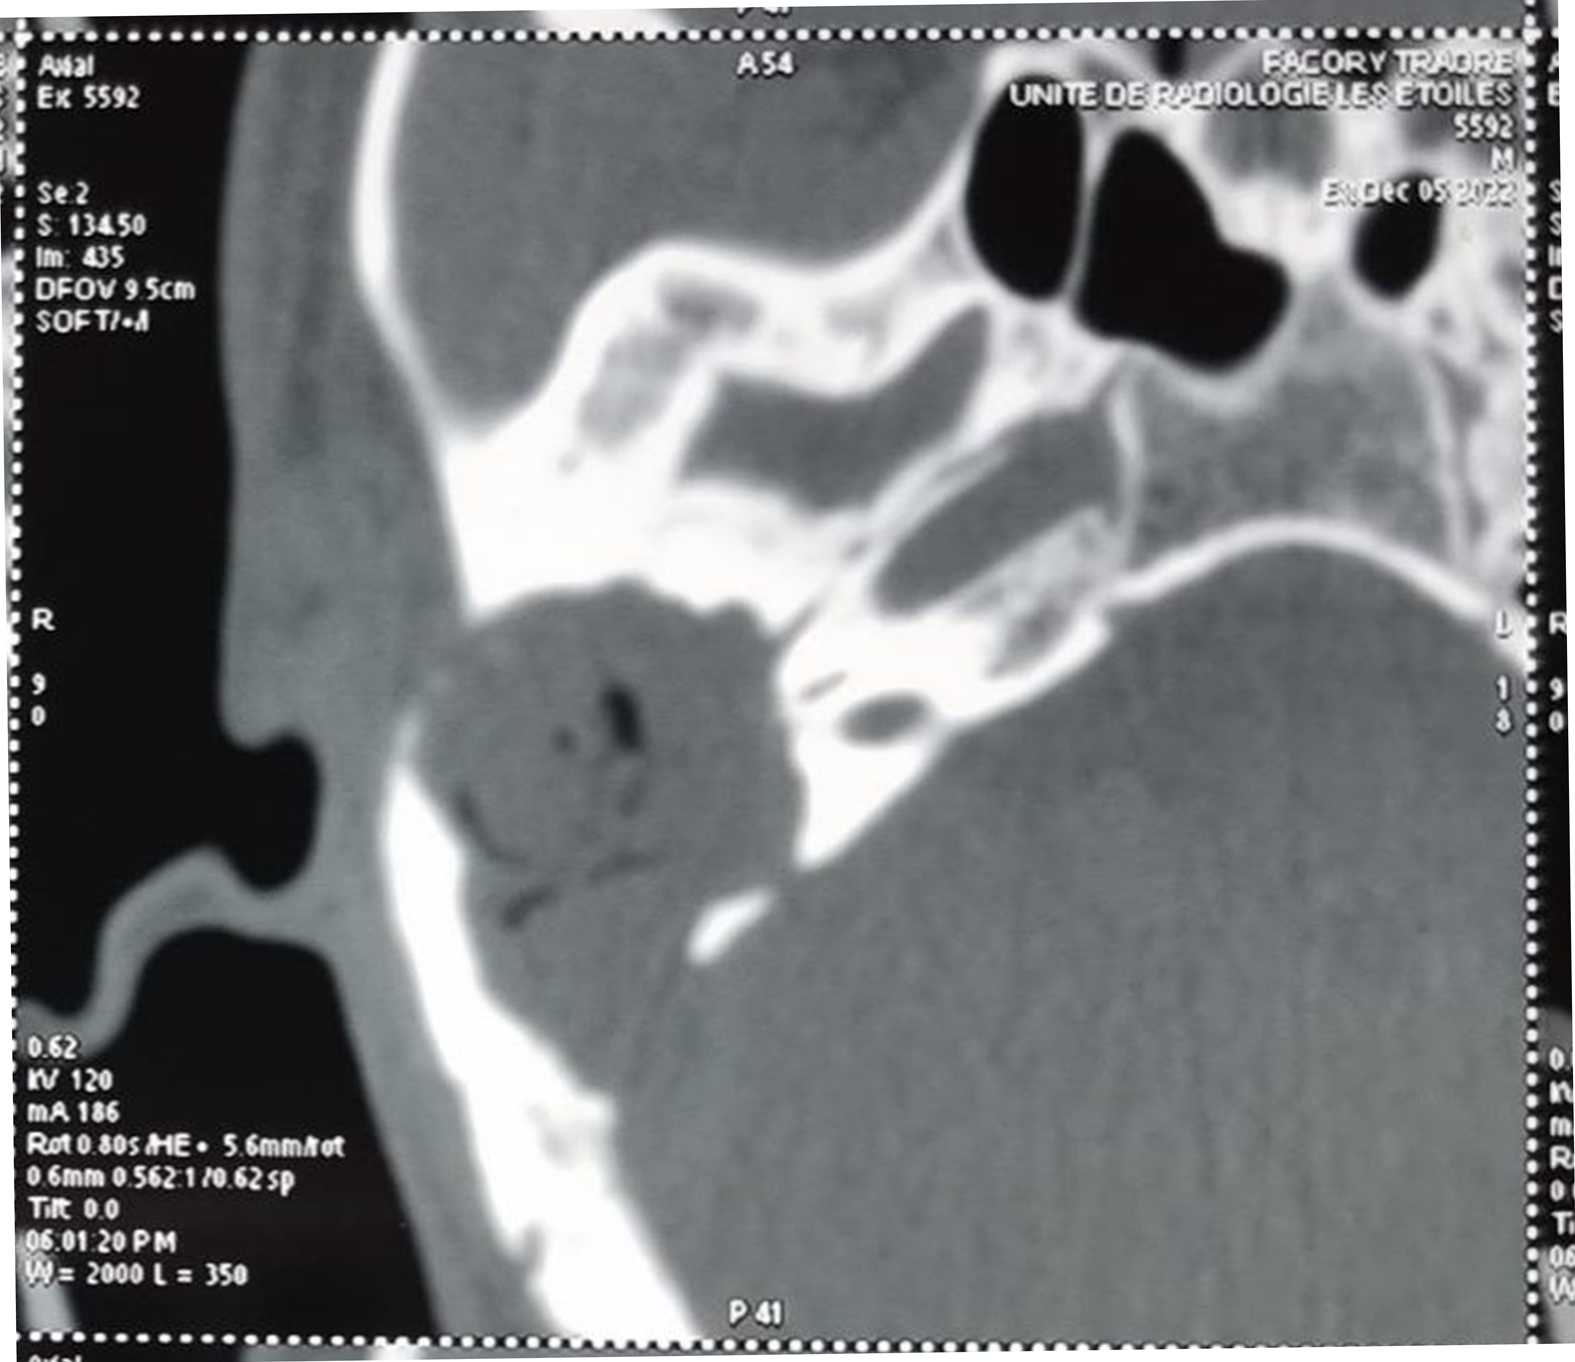

In total, we collected 34 files of patients admitted for cholesteatoma. This represented 9% of cases compared to all otological surgeries carried out during the same period, i.e. 362 cases. The 20 - 40 year old age group was the most represented with 65% (Table 1). The male gender was the most represented in 70.58%. ATCDS of recurrent otitis were the most represented with 75% of cases. The main functional signs were dominated by chronic fetid purulent otorrhea associated with hypoacusis in 94.6% of cases. One case of meningeal complication and three cases of cerebral empyema were reported. Clinically, a postero-superior and marginal tympanic perforation was observed in 53%, a retraction pocket in 5.9%, the sentinel polyp in 9%, and a non-marginal tympanic perforation in 32%. The left ear was the most affected in 67.64%. Conductive hearing loss accounted for 88.23% and mixed hearing loss was 11.77%. The average hearing loss of 40 - 70 dB was the most represented in 61.76% of cases and the average preoperative audiometric Rinne was 35 to 40 dB in 21 cases or 61.76% of cases. The CT of the rocks showed a total filling of the EAC with erosion of the wall of the cubicle and the tympanal bone in one case or 2.94%, a total filling of the middle ear with erosion of the wall of the cubicle and lysis of the ossicular chain in 50.00% of cases, total filling of the middle ear with lysis of the tegmen tympani and extradural empyema in 3 cases or 8.83% (Figure 1, Figure 2), in 2 cases extension was associated with lysis of the facial canal and also 2 cases of lysis of the mastoid cortex. In 6 cases the location was purely attical (Table 2).

Figure 2. CT Rock in sagittal section showing convex tissue hypodensity with lysis ossicles, cubicle wall and thickening of the tegmen tympani.

4.2.2. CT of the Rocks

In our series, the CT of the rocks showed a total filling of the EAC with erosion of the wall of the cubicle and the tympanal bone in one case, i.e. 2.94%, a total filling of the middle ear with erosion of the wall of the ear. the cubicle and lysis of the ossicular chain in 50.00% of cases, total filling of the middle ear with lysis of the tegmen tympani and extradural empyema in 3 cases or 8.83%, in 2 cases the extension was associated with lysis of the facial canal and also 2 cases of lysis of the mastoid cortex. In 6 cases the location was purely attical. Our study is equivalent to those of the authors [3] [7]-[9]. This is explained by the fact that modern imaging currently occupies a preponderant place in the preoperative and postoperative management of ear cholesteatoma [5]. Preoperatively, performing a CT scan is systematically recommended, to clarify the extensions of the cholesteatoma, screen for possible complications, assess the anatomy of the tympanomastoid cavities (in particular the surgical risk variants) and compare the diagnosis. in the rare cases where the otoscopic examination was unable to resolve the problem [6] [10]. As part of the initial assessment of a cholesteatoma of the middle ear, non-enhanced CT is the examination of choice. MRI can sometimes be useful to complement CT data in certain limited indications [3] [11]. Postoperatively, monitoring of operated cholesteatoma has also greatly benefited from advances in modern imaging, with CT and sometimes MRI, making it possible to better identify the indications for surgical revision [3]. Complications, intratemporal and endocranial, can be indicative of cholesteatomatous otitis. These are the complications that make this potentially fatal pathology serious [12].